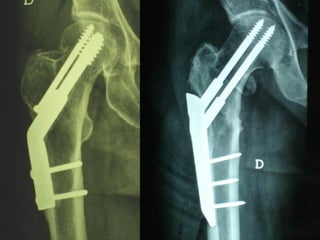

La placca a compressione percutanea (PC.C.P.) di Gotfried è un mezzo di sintesi studiato per assicurare un “impattamento controllato” delle fratture pertrocanteriche grazie alle due viti telescopiche prossimali che garantiscono una ottima stabilità rotazionale

Tradizionalmente si ritiene importante per la stabilità delle fratture pertrocanteriche l’integrità della parte mediale della metafisi prossimale del femore

In realtà la zona più importante per la ricostruzione di questo tipo di fratture è il muro laterale contro il quale si impatta il frammento metaepifisario mediale

Se il muro laterale è rotto o viene lesionato durante la sintesi , come spesso accade in fase di applicazione della vite cefalica dei chiodi endomidollari o della vite-placca, andremo incontro al collasso della frattura e ad un conseguente lungo periodo di impotenza funzionale

Con la placca di Gotfried non si è mai riscontrato un danno iatrogeno del muro laterale e nessun collasso della frattura.Ciò è dovuto al fatto che i fori per l’applicazione delle due viti prossimali sono di piccolo diametro (9 mm) rispetto ai 16-32 mm necessari per introdurre la vite cefalica di un chiodo endomidollare o di una vite-placca a compressione.

La placca PC.C.P. viene inoltre applicata per via percutanea attraverso due piccole incisioni ottenendo in tal modo un minimo trauma chirurgico ed una  perdita di sangue estremamente ridotta in pazienti che per l’età  sono già in condizioni  critiche

Dal Gennaio 2005 ad Agosto 2006 110  placche di Gotfried Età media  : 78 anni (range 29-94) Tempo chirurgico: 30 minuti (range 12-45) IMMEDIATA CONCESSIONE DEL CARICO